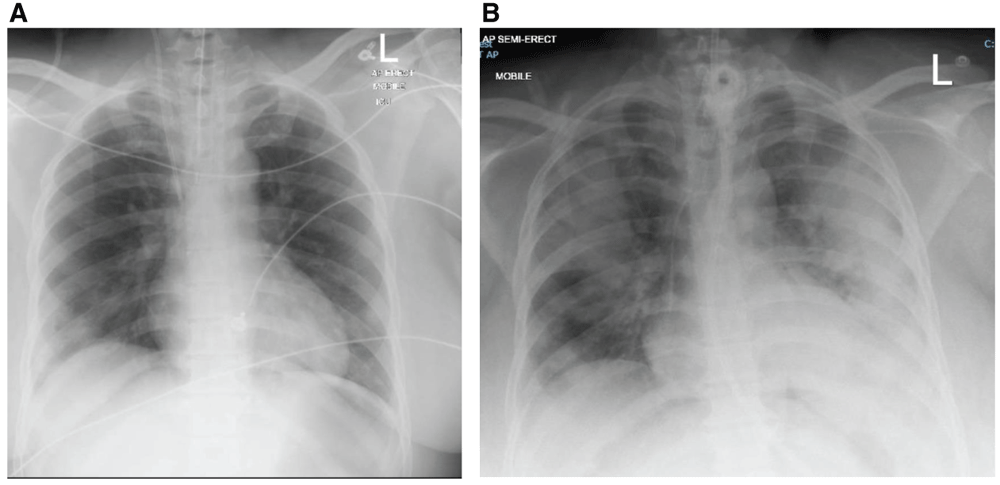

A 45-year-old female with poorly controlled, insulin-dependent diabetes mellitus (with retinopathy), hypothyroidism and central adiposity presented to our emergency department in extremis, in diabetic ketoacidosis, severely dehydrated and agitated following two days of cough and anorexia. The cough was non-productive. Arterial blood gas results included pH 6.91, Base -26, blood sugar level was high (unrecordable) and ketones were elevated at 5 mmol/L. A size 7.0-mm cuffed oral endotracheal tube was chosen to permit invasive ventilation and bronchoscopy if required; Cormac & Lehane view was Grade 2 and the tube was fixed at 23 cm from the lips. Initial CXR, Figure 3a. Medications on presentation were metformin 1 g twice daily, Lantus & Novorapid (variable doses) and levothyroxine 100 µg once daily.

(A) Post-intubation plain chest radiograph, on day 1 of hospital admission. (B) Day 5 following re-intubation.

On day 5 of admission, the ETT was removed in a trial of extubation. She was stridulous, not improving with nebulised adrenaline and intravenous corticosteroids, and progressively developed increased work of breathing. She was re-intubated (again size 7) several hours later and started on regular dexamethasone 6.6mg TDS. Subsequent CXR, Figure 3b.